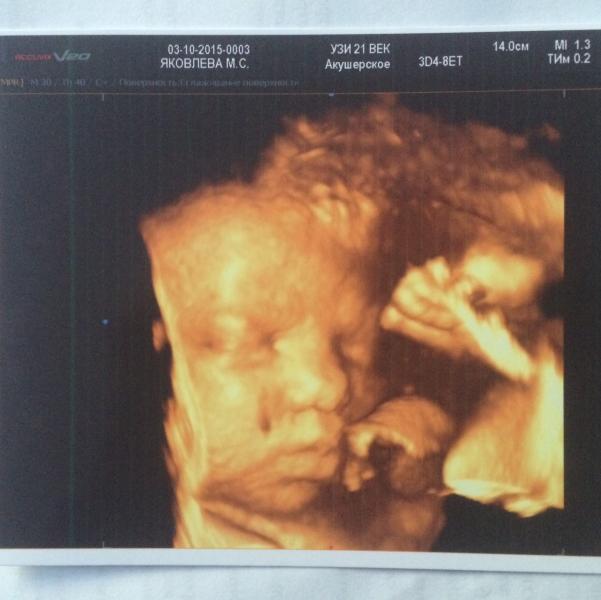

По ходу я выспалась... Ну что, сходили мы вчера на внеплановый скрининг, т.к в ЖК мне решили его сдалась на 29 недели, но, в принципе, мы и так собирались делать платно, чтоб папа мог увидеться с дочей. В очередной раз я готова петь дифирамбы аппаратуре в клинике "узи 21 век" и ее врачам, всё таки они узкие специалисты, и по мне смотрят тщательнее... В общем, доча весит 2310, за 4 недели поправилась на 710 грамм!!! 😳 щеки уже передавливают нос...😂 как всегда пыталась спрятаться в стенке, потом ...